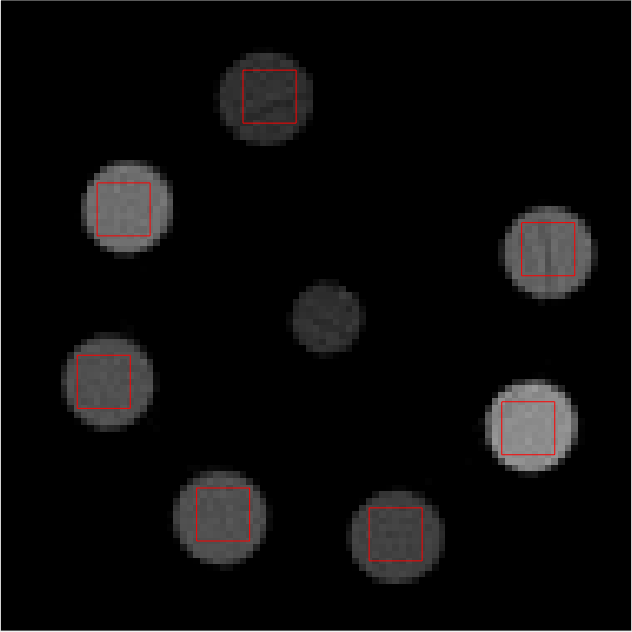

Individual reconstructions from every bin were first performed with scalar MBIR. This furnished 555 LAC images, each from a different energy bin. 101010 slices of each LAC image volume were used to compute \mathcal{M}. The mixing matrix was computed from ROIs shown in red in Fig 2. The following equation must be satisfied ideally

Refer to caption

(a)

(b)

(c)

(d)

(e)

Figure 2: Middle slice of LAC image reconstruction of each energy bin sinogram for mixing matrix estimation. Display window [0, 0.1]

LABEL:sub@fig:En1 Bin1:7.019.0keV7.019.0𝑘𝑒𝑉7.0-19.0\ keV, LABEL:sub@fig:En2 Bin2: 19.029.0keV19.029.0𝑘𝑒𝑉19.0-29.0\ keV, LABEL:sub@fig:En3 Bin3: 29.038.8keV29.038.8𝑘𝑒𝑉29.0-38.8\ keV, LABEL:sub@fig:En4 Bin4: 38.851.1keV38.851.1𝑘𝑒𝑉38.8-51.1\ keV, LABEL:sub@fig:En5 Bin5: 51.182.6keV51.182.6𝑘𝑒𝑉51.1-82.6\ keV

Some of the individual reconstructed LAC images have ring artifacts and some have circular bands that have voxels with clearly different LAC value from their neighbors. This is caused by inconsistent behavior of some detectors and contributes to error in the estimate of material fraction’s average values within the ROI. Another potential source of error could be the noise in mixing matrix from the calibration dataset as pointed out in [3]. Inter-material difference in material fraction values was not penalized in the regularizer term U(xl)𝑈subscript𝑥𝑙U(x_{l}) but will be explored in future work.